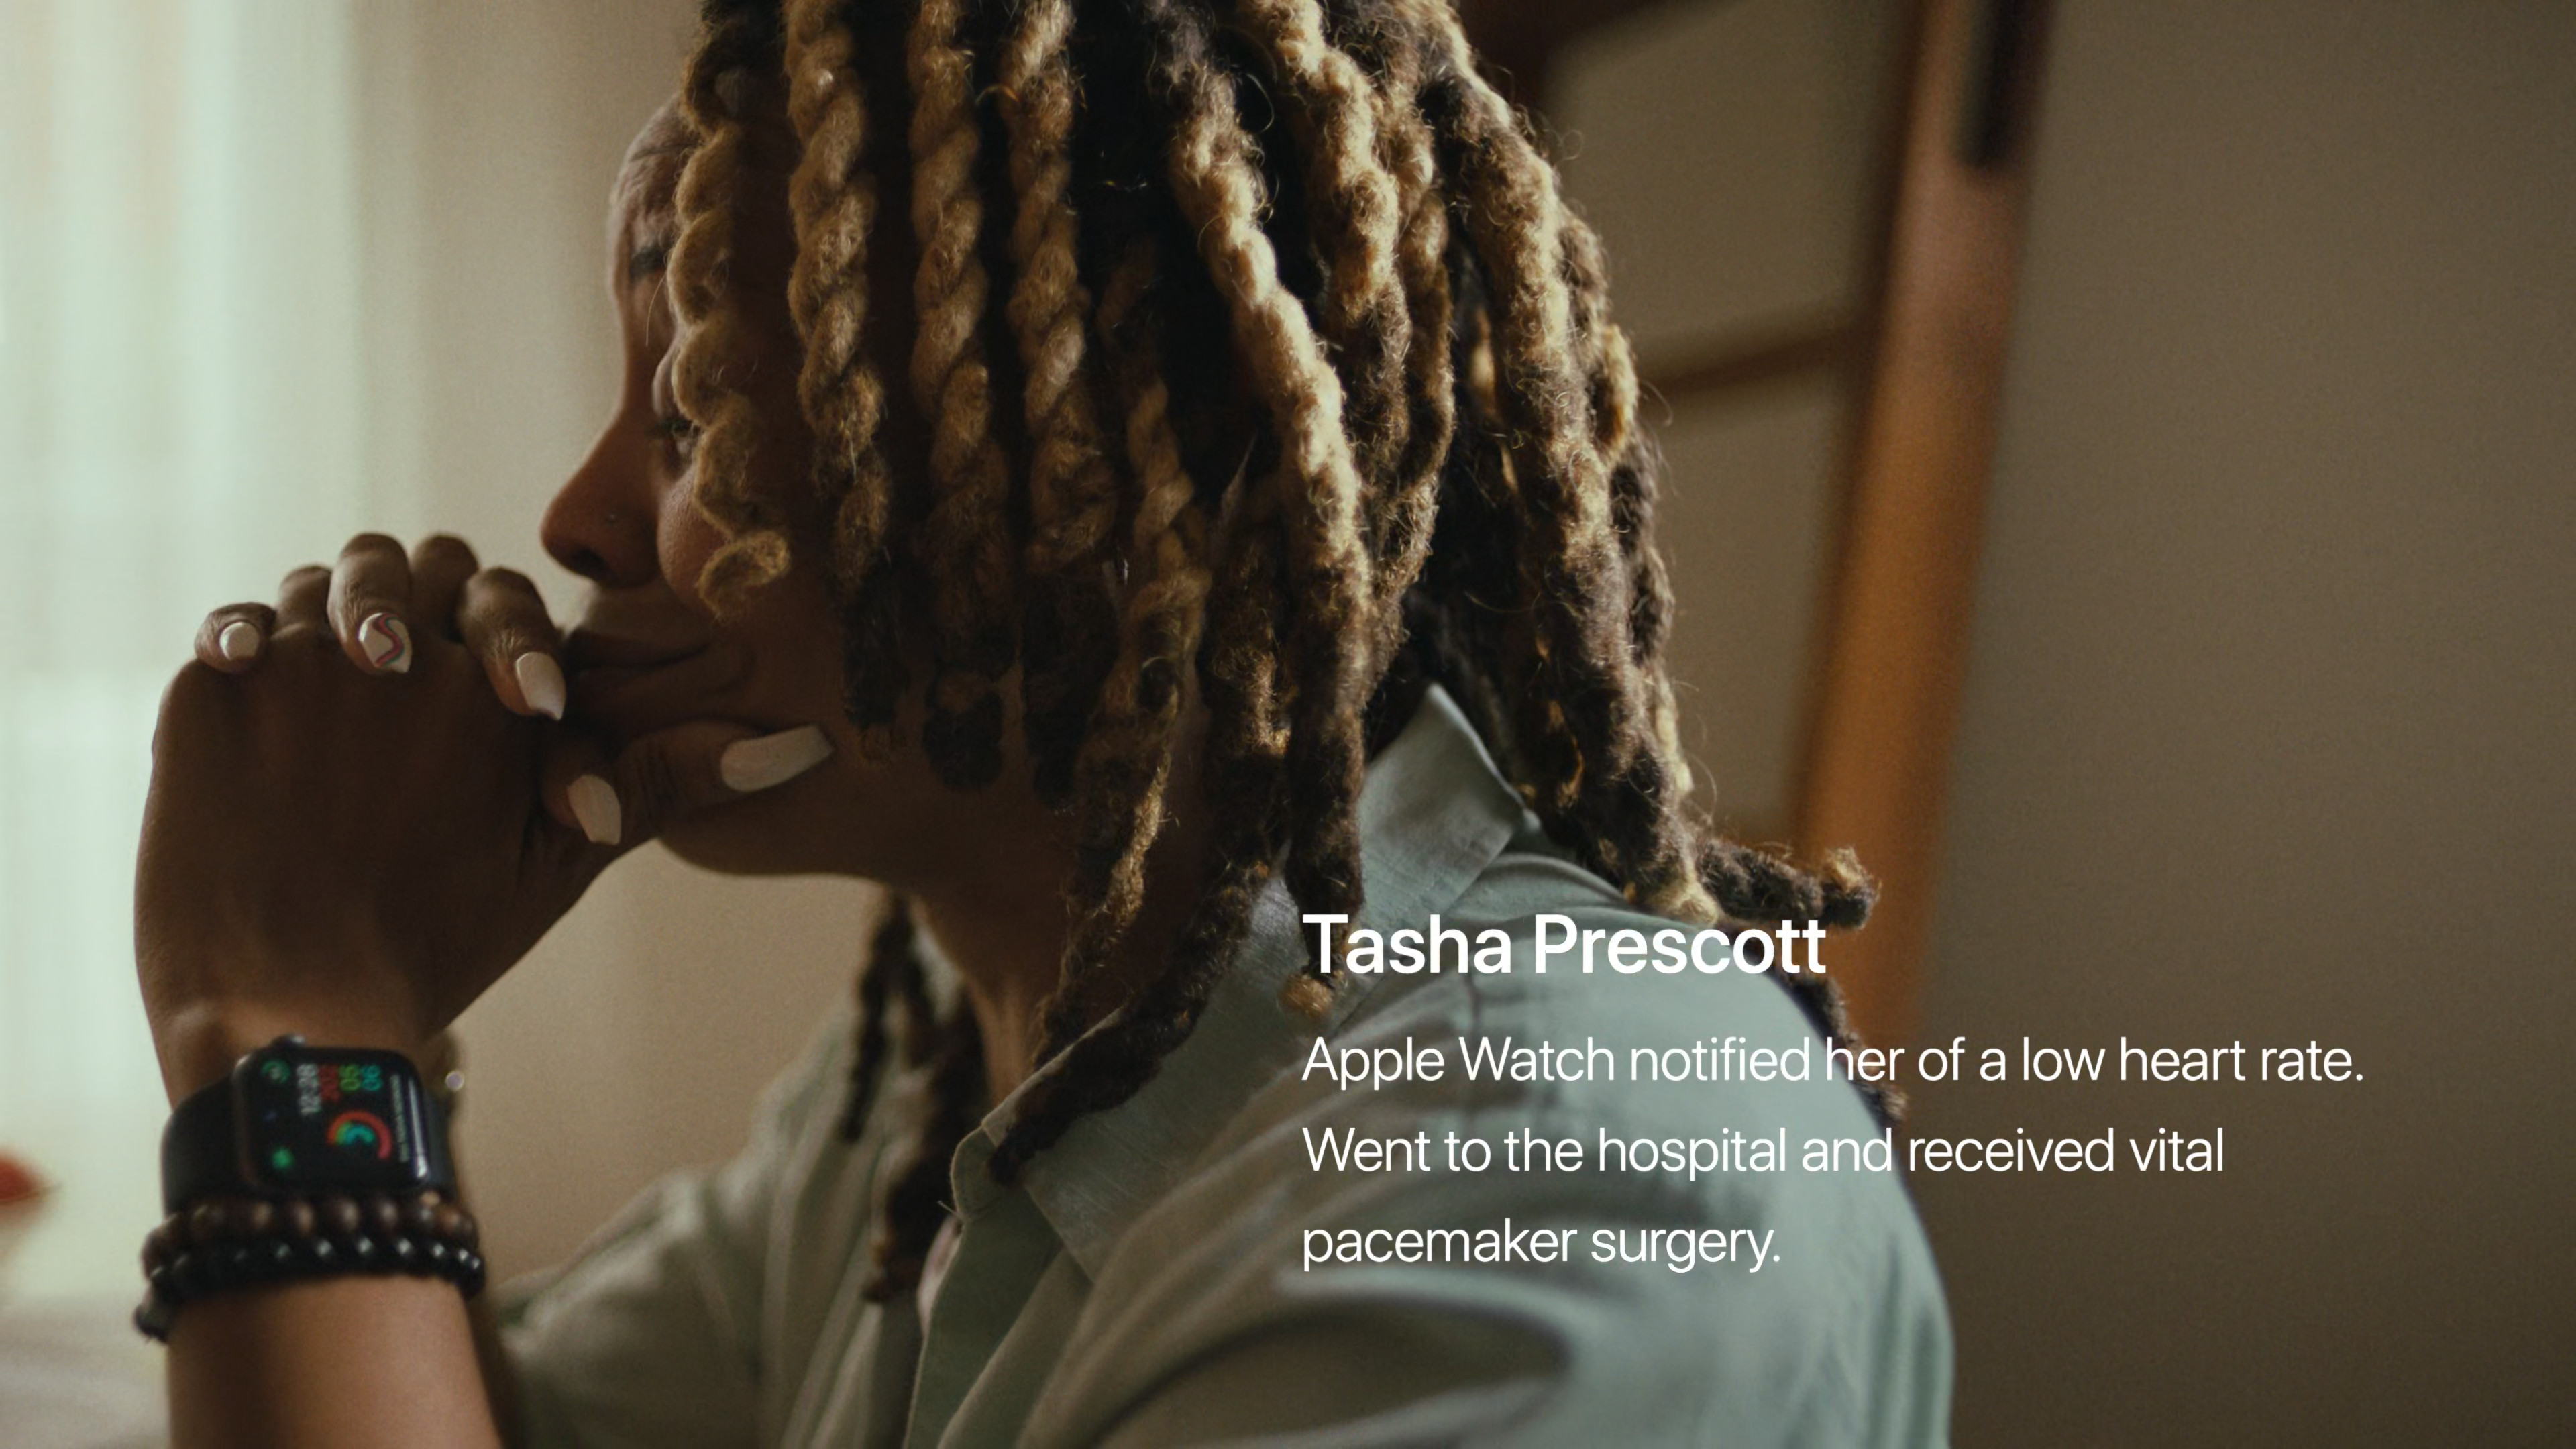

Již několik desítek minut před začátkem se na webu Applu objevilo logo letošní Keynote za doprovodu skladby Natural od Jackie Mendozy a Magic in U od Cub Sport. Jakmile odbila sedmá, animace se změnila v tradiční úvodní video se záběry na různé lidi, jak v průběhu dne od probuzení až do noci používají nejrůznější Apple zařízení. Po přehrání emotivního videa, zmiňujícího mimo jiné přínos Apple Watch a dalších jablečných produktů a jejich funkcí pro lidské zdraví, jsme se mohli pokochat klasickým přeletem nad Apple Parkem. V němž nás již přivítal Tim Cook a zahájil nejdůležitější Apple Keynote letošního roku, na které se představí iPhone 15, iPhone 15 Pro (Max), Apple Watch Series 9 a spousta dalších novinek.